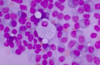

Describe the appearane of neutrophils.

Multilobed nuclei with lots of granules

Describe the appearance of eosinophils.

Bi-lobed nucleus with red granules